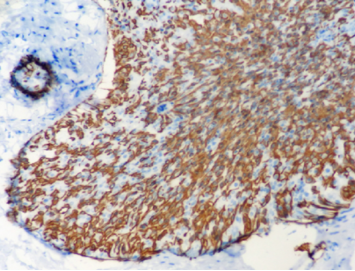

免疫组化

ER弥漫强+,Her2-,ki67低表达

具有神经内分泌表达:CgA、Syn(约70%的比例,阳性细胞表达不等)

CK5/6、CKH-,可斑驳性的残留

肌上皮内-,导管周可-可+